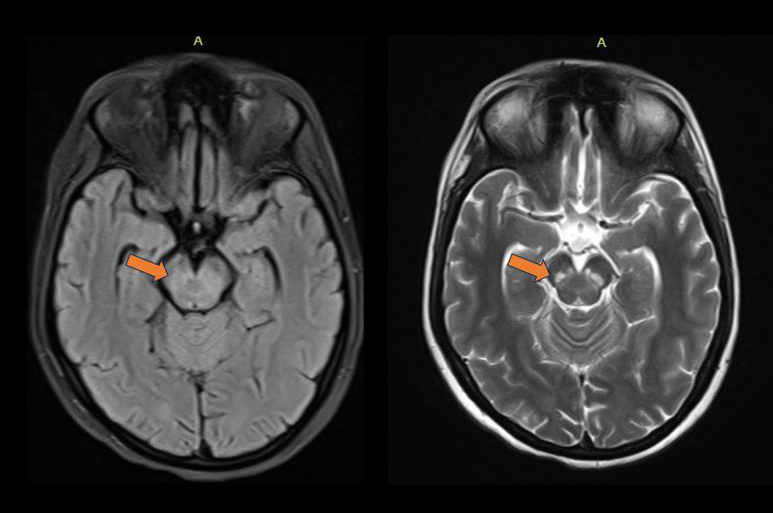

Figure 4: MRI Brain(T2/FLAIR): Bilateral symmetrical hyperintense lesion

showing atrophy and calcification of substantia nigra.

progressed to severe neurobehavioral, extrapyramidal, and bulbar

Behavioural disturbance like altered sensation and mood disturbance

suggests the involvement of thalamus (supratentorial region).